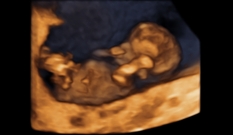

O rosto vai adquirindo suas características e se parece cada vez mais com o de um bebê. Os olhos, no começo da gravidez, ficam muito separados, mas vão movendo-se para o centro do rosto. As orelhas vão adquirindo a forma que conhecemos — algumas semanas antes, ainda estavam bem atrás na cabeça, mas, agora, estão um pouco abaixo dos olhos.

Ainda é possível fazer o ultrassom do primeiro trimestre e, neste caso, tudo o que explicamos na semana anterior segue valendo. Na maioria das pacientes, os primeiros exames da gravidez já foram feitos — já passamos por um dos principais momentos em que se verificou que está tudo bem.

| Já passamos por um dos grandes momentos da gravidez, o ultrassom do primeiro trimestre, no qual se verificou que estava tudo bem. |